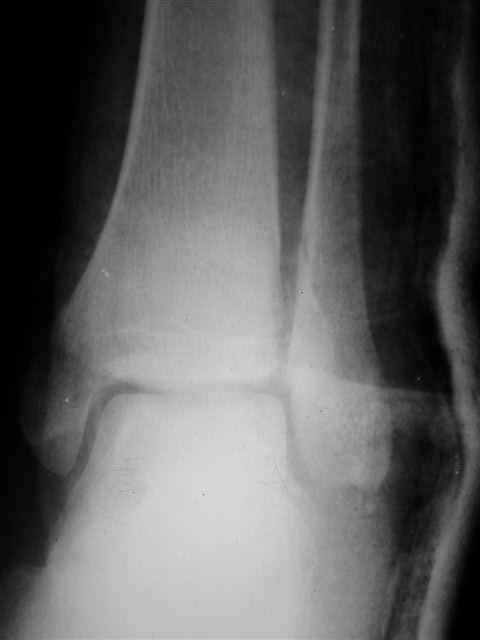

> Если Вас не затруднит, пришлите, пожалуйста, рентгенограммы. Я

> интересуюсь тактикой лечения повреждений голеностопного сустава.

Ничего сверхъестественного, но если есть интерес, то в понедельник пересниму Рг-граммы и отправлю.

Я предупреждал, что ничего сверхъестественного. Каюсь, что одна из спиц прошла несколько дальше, чем нужно было, но главное - перелом стабилизирован и больной работает суставом в полном объёме, несмотря на представленную раннее травму коленного сустава.